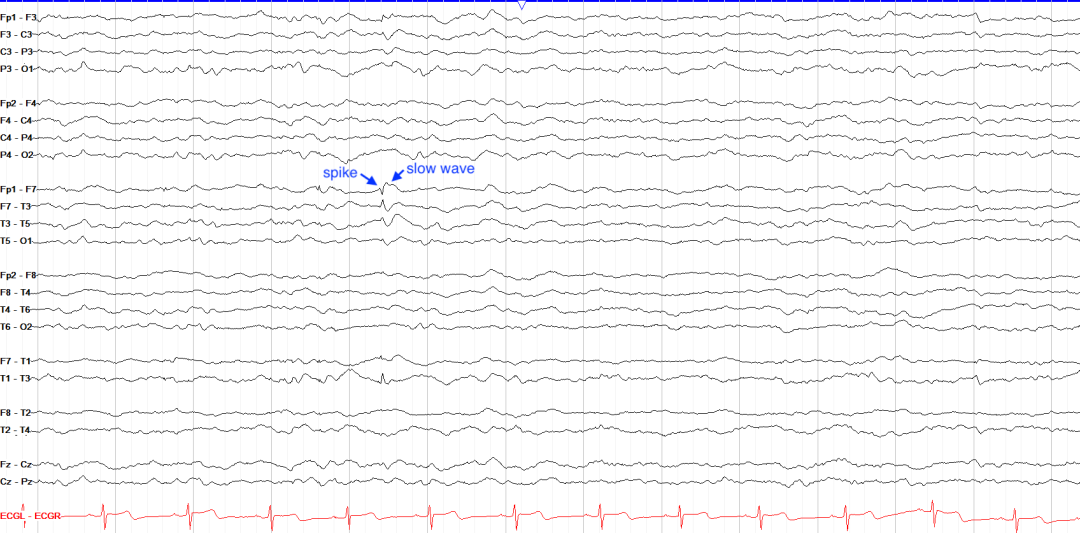

尖波和棘波是癫痫样活动的基本单元,表现为短暂、高幅的异常放电。

时域特征为单相或双相波形,持续时间短(20-70 ms),振幅通常高于背景活动(≥70 μV),形态陡峭,常伴后随慢波。

波形与棘波相似,但持续时间较长(70-200 ms),上升支略缓,下降支陡峭,其后亦多跟随慢波。

在棘波或尖波后出现的宽大负向波,持续时间200-500 ms,反映神经元同步化放电后的超极化抑制期。慢波振幅常高于前导棘/尖波,构成经典的“棘慢复合波”或“尖慢复合波”。

棘波与尖波均为皮层超兴奋性标志,但两者在癫痫严重程度上无明确差异。单一放电需结合临床背景解读:无癫痫病史者偶发棘/尖波可能为良性变异,而癫痫患者中则提示致痫网络存在。